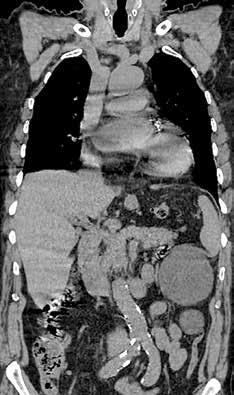

In November 2022, I attended my fourth Australasian Gastro-Intestinal Trials Group (AGITG) Annual Scientific Meeting (ASM). This meeting brings together oncologists, radiation oncologists, surgeons and scientists who present and discuss the latest in Australasian trials, current clinical dilemmas and future directions in gastrointestinal cancer. I first attended this meeting in 2015 and was overawed, humbled and inspired by the more than 400 people gathered, discussing the possible future of improved patient outcomes. However, I reported that only a third of MRI rectal scans in our cohort met image quality standards and included the required data for reporting.1 In addition, while most trials required imaging to stratify patients to test their new treatments, I was the only radiologist in the room.